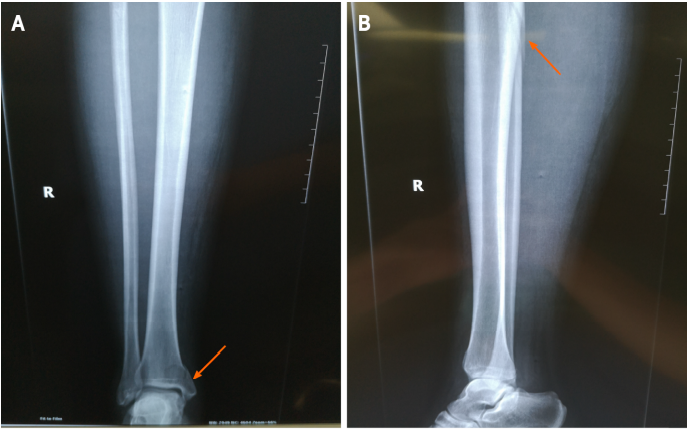

1位31岁女性患者在5天前步行时不小心扭伤了右脚踝。小腿的全长X线片显示腓骨近端骨折,下胫腓关节分离,内踝骨折累及后踝。磁共振成像显示胫腓前下韧带和距腓前韧带断裂。我们诊断出一种罕见的Maisonneuve骨折类型,合并腓骨近端骨折、下胫腓关节分离、内踝骨折以及胫腓前下韧带和距腓前韧带断裂。患者接受切开复位内固定术,术后6个月随访,临床效果良好。此患者同时具有旋前外旋踝关节骨折和旋后内收踝关节骨折的特点。本例腓骨骨折呈长斜骨折,骨折线靠近腓骨。还有下胫腓分离。这些特征与典型的Maisonneuve骨折相似,后者是一种旋前外旋踝关节骨折。而内踝典型的旋前外旋踝关节骨折通常表现为三角韧带的斜位断裂,而不表现为距腓前韧带或跟腓断裂(11)。本例踝内侧骨折为垂直骨折,距腓骨前韧带断裂,与旋后内收踝关节骨折一致。

图1;A:术前踝关节和小腿正位X线片(箭头);B:术前踝关节和小腿侧位X线片(箭头)。小腿全长X线片显示腓骨近端骨折(箭头)和内踝骨折(箭头)